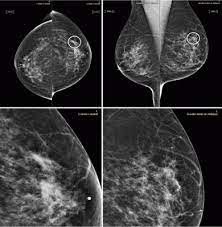

How Does Breast Cancer Look Like On A Mammogram / Mammogram Images Normal Abnormal And Breast Cancer : The outer edges of these cells look fuzzy or spiky (called spiculated).. Healthy mammograms can still vary in appearance. That makes it easy to detect abnormalities, which generally show up as white. If found in an area of rapidly dividing cells or grouped together in a certain way, they may be a sign of dcis or breast. A lump or tumor will show up as a focused white area on a mammogram. Dense breast tissue appears solid.

Breast Masses Cancerous Tumor Or Benign Lump from www.verywellhealth.com Even if you have a lump in only one breast, pictures will be taken of both breasts. This appears most commonly as streaking, known as linear enhancement. A woman's breast tissue also changes over time, and it is not uncommon for benign lumps, cysts or calcifications to form with age. Breast cancer can appear as a spiculated mass, cluster of tiny calcifications, smoothly marginated mass, area of subtle distortion or be invisible on. What does an abnormal mammogram look like? Cancer cells can remain within the milk ducts and this is considered as noninvasive cancer or ductal carcinoma in situ. Magnetic resonance imaging (mri) of the breast — or breast mri — is a test used to detect breast cancer and other abnormalities in the breast. The appearance of normal breast tissue on a mammogram varies from person to person, and no two mammograms look the same.

Breast Cancer Ge News from www.ge.com Healthy mammograms can still vary in appearance. The dye collection in the breast can also look clumpy or appear in a section of the breast, depending on the involvement of dcis. It can also be used to investigate the cause of breast problems, such as a breast mass, pain and nipple. Cancers may be seen as masses (like a ball, but usually with an irregular shape), areas of asymmetry that resemble normal tissue, calcifications (white specks), and/or areas of architectural distortion (imagine the puckering caused by pulling a thread in a piece of fabric). There are few risks associated with mammography. If you've had a mammogram before, the radiologist should compare your old mammogram to the new one to look for changes. After a mammogram that didn't show anything, and a sonogram that found the lump, i was diagnosed with stage 2 breast cancer. The doctor reading your mammogram will be looking for different types of breast changes, such as small white spots called calcifications, larger abnormal areas called masses, and other suspicious areas that could be signs of cancer.

Microcalcifications, which look like white specks on a mammogram. They will look carefully at the mammogram to interpret the results. Tumor size is an important factor in breast cancer staging, and it can affect a person's treatment options and outlook. Breast mri images are combined, using a computer, to create detailed pictures. Breast cancer can appear as a spiculated mass, cluster of tiny calcifications, smoothly marginated mass, area of subtle distortion or be invisible on. Magnetic resonance imaging (mri) of the breast — or breast mri — is a test used to detect breast cancer and other abnormalities in the breast. Calcifications are calcium deposits within the breast tissue and they look like small white spots. A breast cancer tumor on a mammogram is often irregular with edges that don't look smooth. A 3d mammogram is used to look for breast cancer in people who have no signs or symptoms. A rash isn't the only visual symptom of inflammatory breast cancer. A mammogram can show breast changes such as calcifications, masses, or other symptoms that might be cancer. This appears most commonly as streaking, known as linear enhancement. What does cancer look like on a mammogram?

This appears most commonly as streaking, known as linear enhancement. As with all abnormalities seen on breast imaging, the diagnosis of dcis requires a sample of tissue or biopsy. What does breast cancer look like on a mammogram? Calcifications are calcium deposits within the breast tissue and they look like small white spots. Breast cancer can appear as a spiculated mass, cluster of tiny calcifications, smoothly marginated mass, area of subtle distortion or be invisible on.

Mammogram Images Normal And Abnormal from www.verywellhealth.com Any area that does not look like normal tissue is a possible cause for concern. The appearance of normal breast tissue on a mammogram varies from person to person, and no two mammograms look the same. A woman's breast tissue also changes over time, and it is not uncommon for benign lumps, cysts or calcifications to form with age. What does cancer look like on a mammogram? Tumors may be benign or cancerous. Abnormalities such as cancerous tumors usually appear brighter because they are denser. Cancers may be seen as masses (like a ball, but usually with an irregular shape), areas of asymmetry that resemble normal tissue, calcifications (white specks), and/or areas of architectural distortion (imagine the puckering caused by pulling a thread in a piece of fabric). Calcifications are calcium deposits within the breast tissue and they look like small white spots.

Any area that does not look like normal tissue is a possible cause for concern. Invasive breast cancer can appear as a white patch or mass on a mammogram. You may notice dimpling or pitting, and the skin on your breast. A rash isn't the only visual symptom of inflammatory breast cancer. The milk ducts carry your breast milk from lobules, where milk is produced, to your nipple. Magnetic resonance imaging (mri) of the breast — or breast mri — is a test used to detect breast cancer and other abnormalities in the breast. A lump or tumor will show up as a focused white area on a mammogram. 1 the gray areas correspond to normal fatty tissue, while the white areas are normal breast tissue with ducts and lobes. A spiculated breast mass, which has spikes extending out from the main mass, is often highly suggestive of cancer. Macrocalcifications, which look like small white dots on a mammogram. It's so important to listen to the messages our bodies are telling. In addition to mammograms, ultrasound and mri may also be used to take a closer look at changes in the breast. Breast cancer can appear as a spiculated mass, cluster of tiny calcifications, smoothly marginated mass, area of subtle distortion or be invisible on.